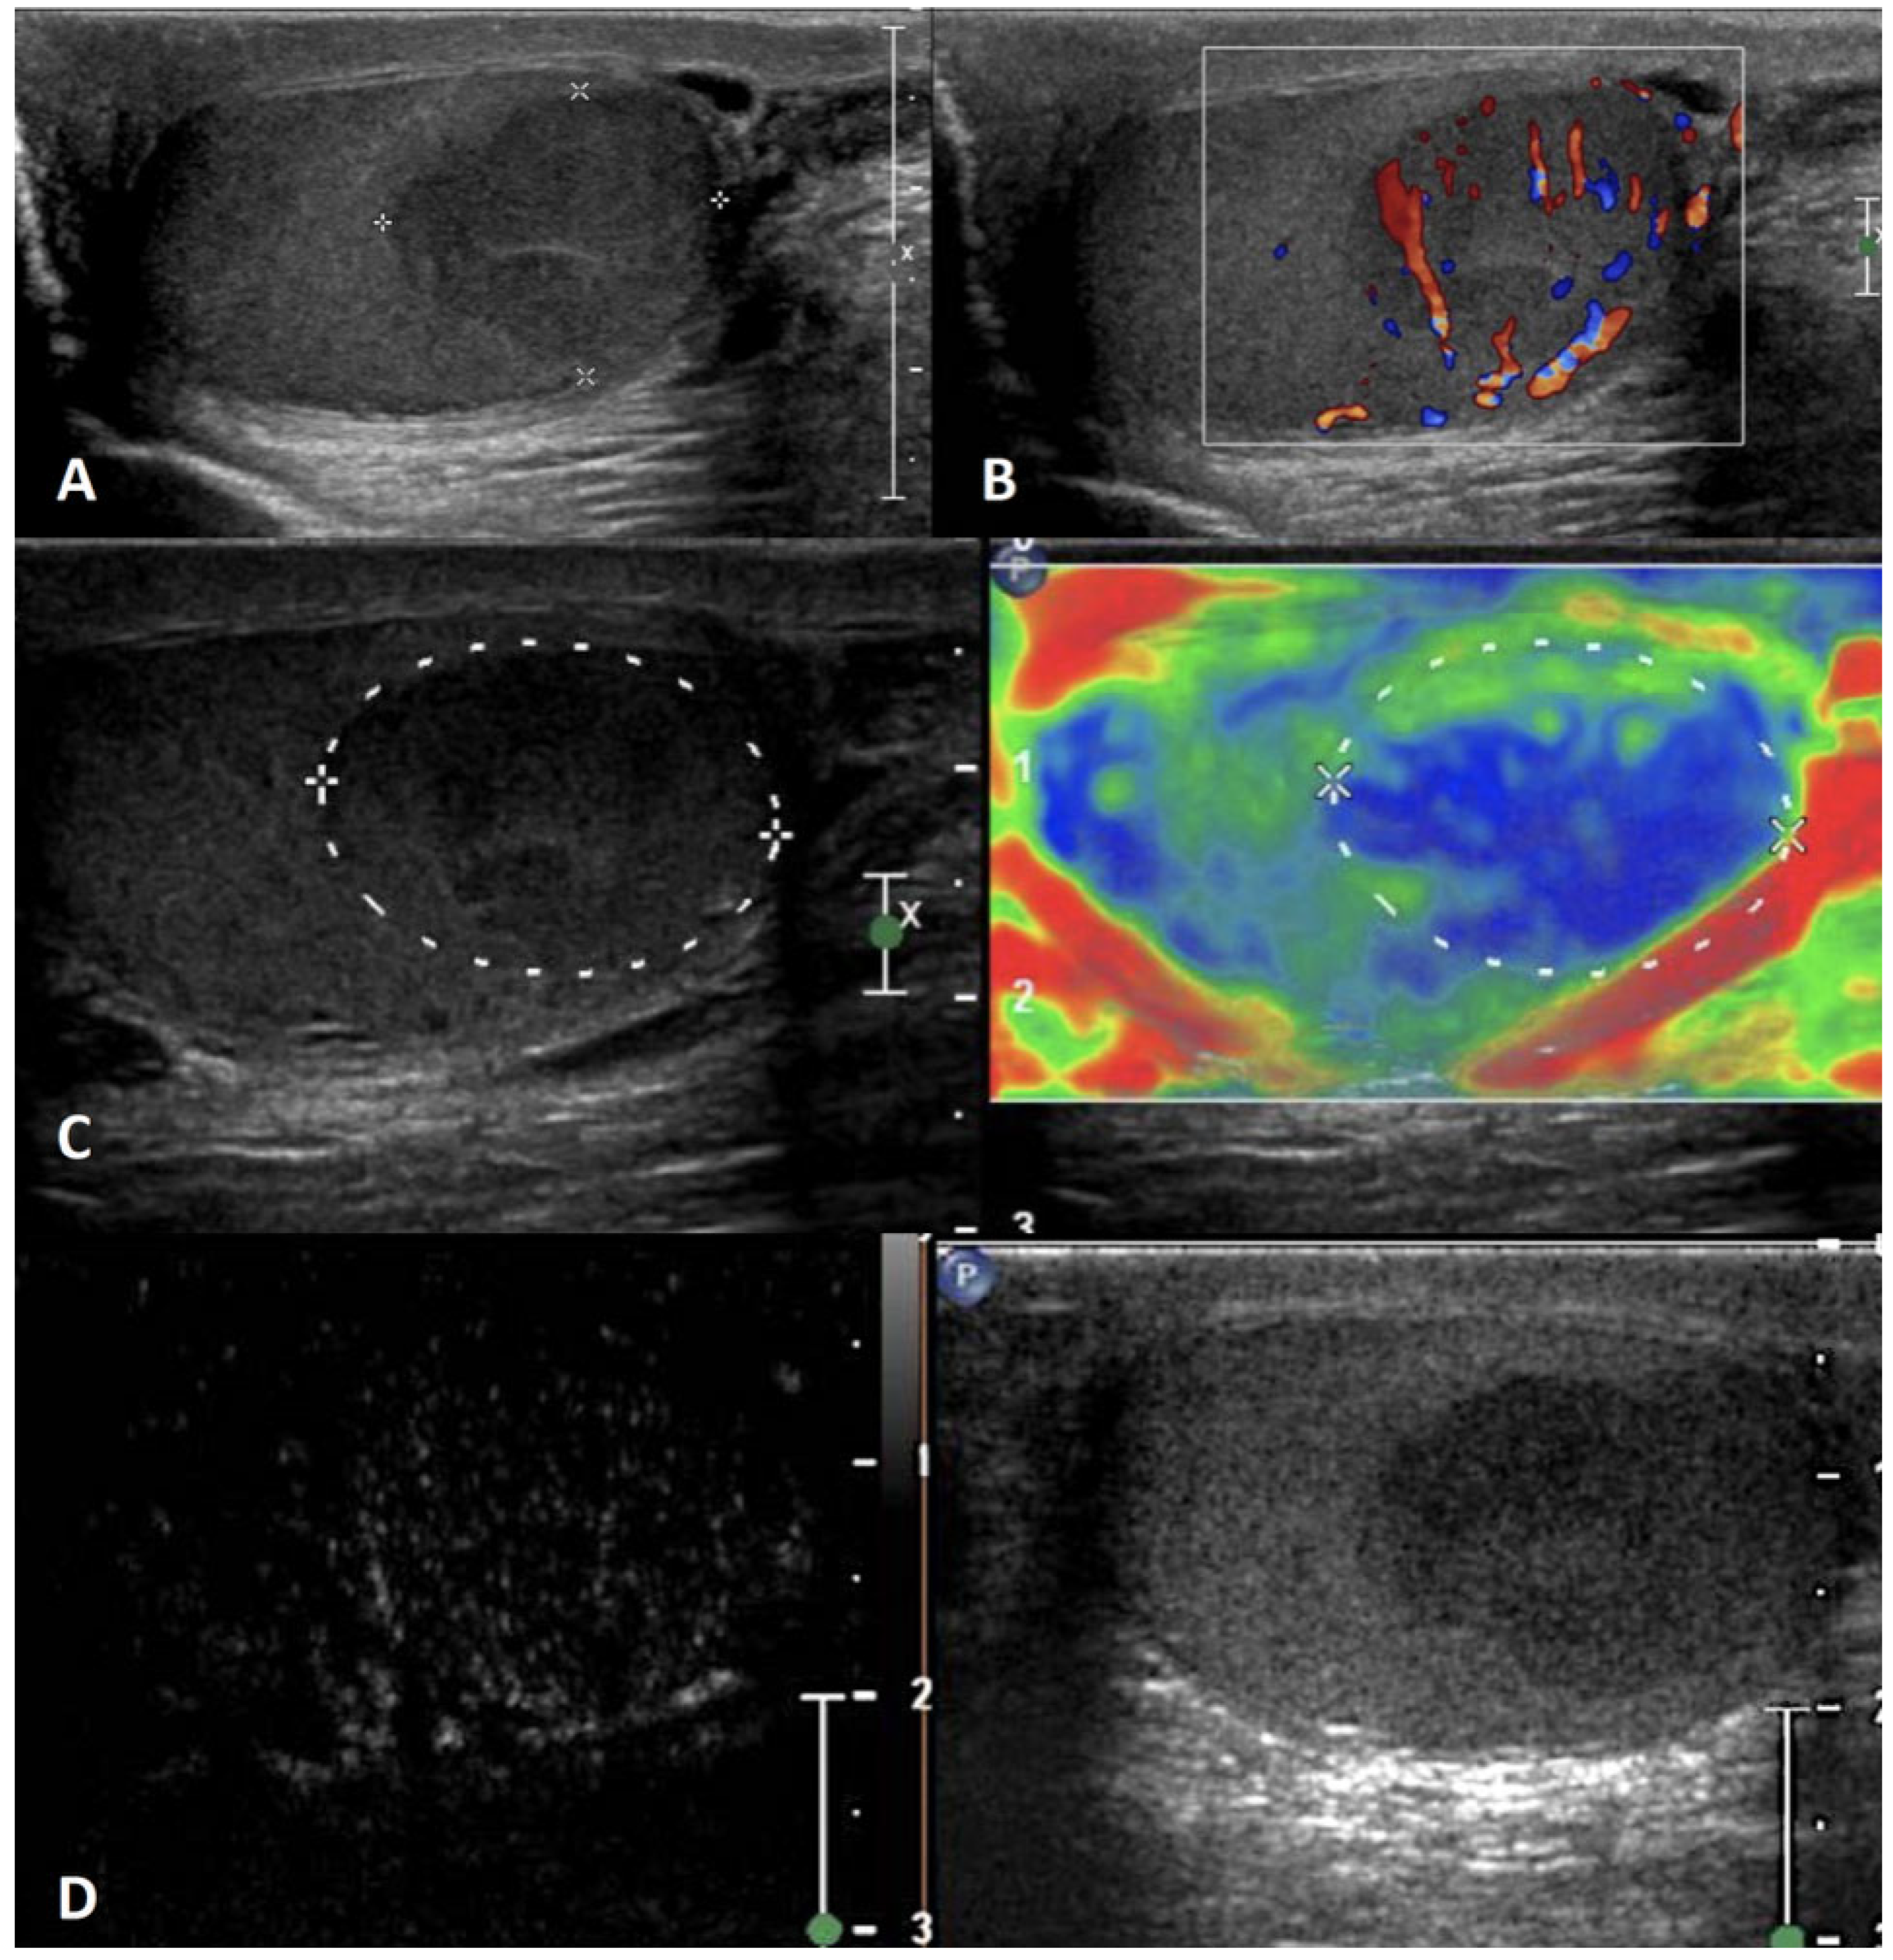

4.5. Segmental Testicular Infarction

- Patel, K.V.; Huang, D.Y.; Sidhu, P.S. Metachronous Bilateral Segmental Testicular Infarction: Multi-Parametric Ultrasound Imaging with Grey-Scale Ultrasound, Doppler Ultrasound, Contrast-Enhanced Ultrasound (CEUS) and Real-Time Tissue Elastography (RTE). J. Ultrasound 2014, 17, 233–238. [Google Scholar] [CrossRef] [PubMed]

- Bilagi, P.; Sriprasad, S.; Clarke, J.L.; Sellars, M.E.; Muir, G.H.; Sidhu, P.S. Clinical and Ultrasound Features of Segmental Testicular Infarction: Six-Year Experience from a Single Centre. Eur. Radiol. 2007, 17, 2810–2818. [Google Scholar] [CrossRef] [PubMed]

- Fernández-Pérez, G.C.; Tardáguila, F.M.; Velasco, M.; Rivas, C.; Dos Santos, J.; Cambronero, J.; Trinidad, C.; San Miguel, P. Radiologic Findings of Segmental Testicular Infarction. AJR Am. J. Roentgenol. 2005, 184, 1587–1593. [Google Scholar] [CrossRef]

- Bertolotto, M.; Derchi, L.E.; Sidhu, P.S.; Serafini, G.; Valentino, M.; Grenier, N.; Cova, M.A. Acute Segmental Testicular Infarction at Contrast-Enhanced Ultrasound: Early Features and Changes during Follow-Up. AJR Am. J. Roentgenol. 2011, 196, 834–841. [Google Scholar] [CrossRef]

| Segmental infarction | Idiopathic or consequent to surgery, inflammatory events, blood disorders or autoimmune diseases; usually acute painful swollen scrotum OR asymptomatic | Hypoechoic wedge-shaped or roundish area | Avascular OR peripheral rim of low CD | Unenhanced/ perilesional rim enhancement | Soft lesions with high elastic strain |